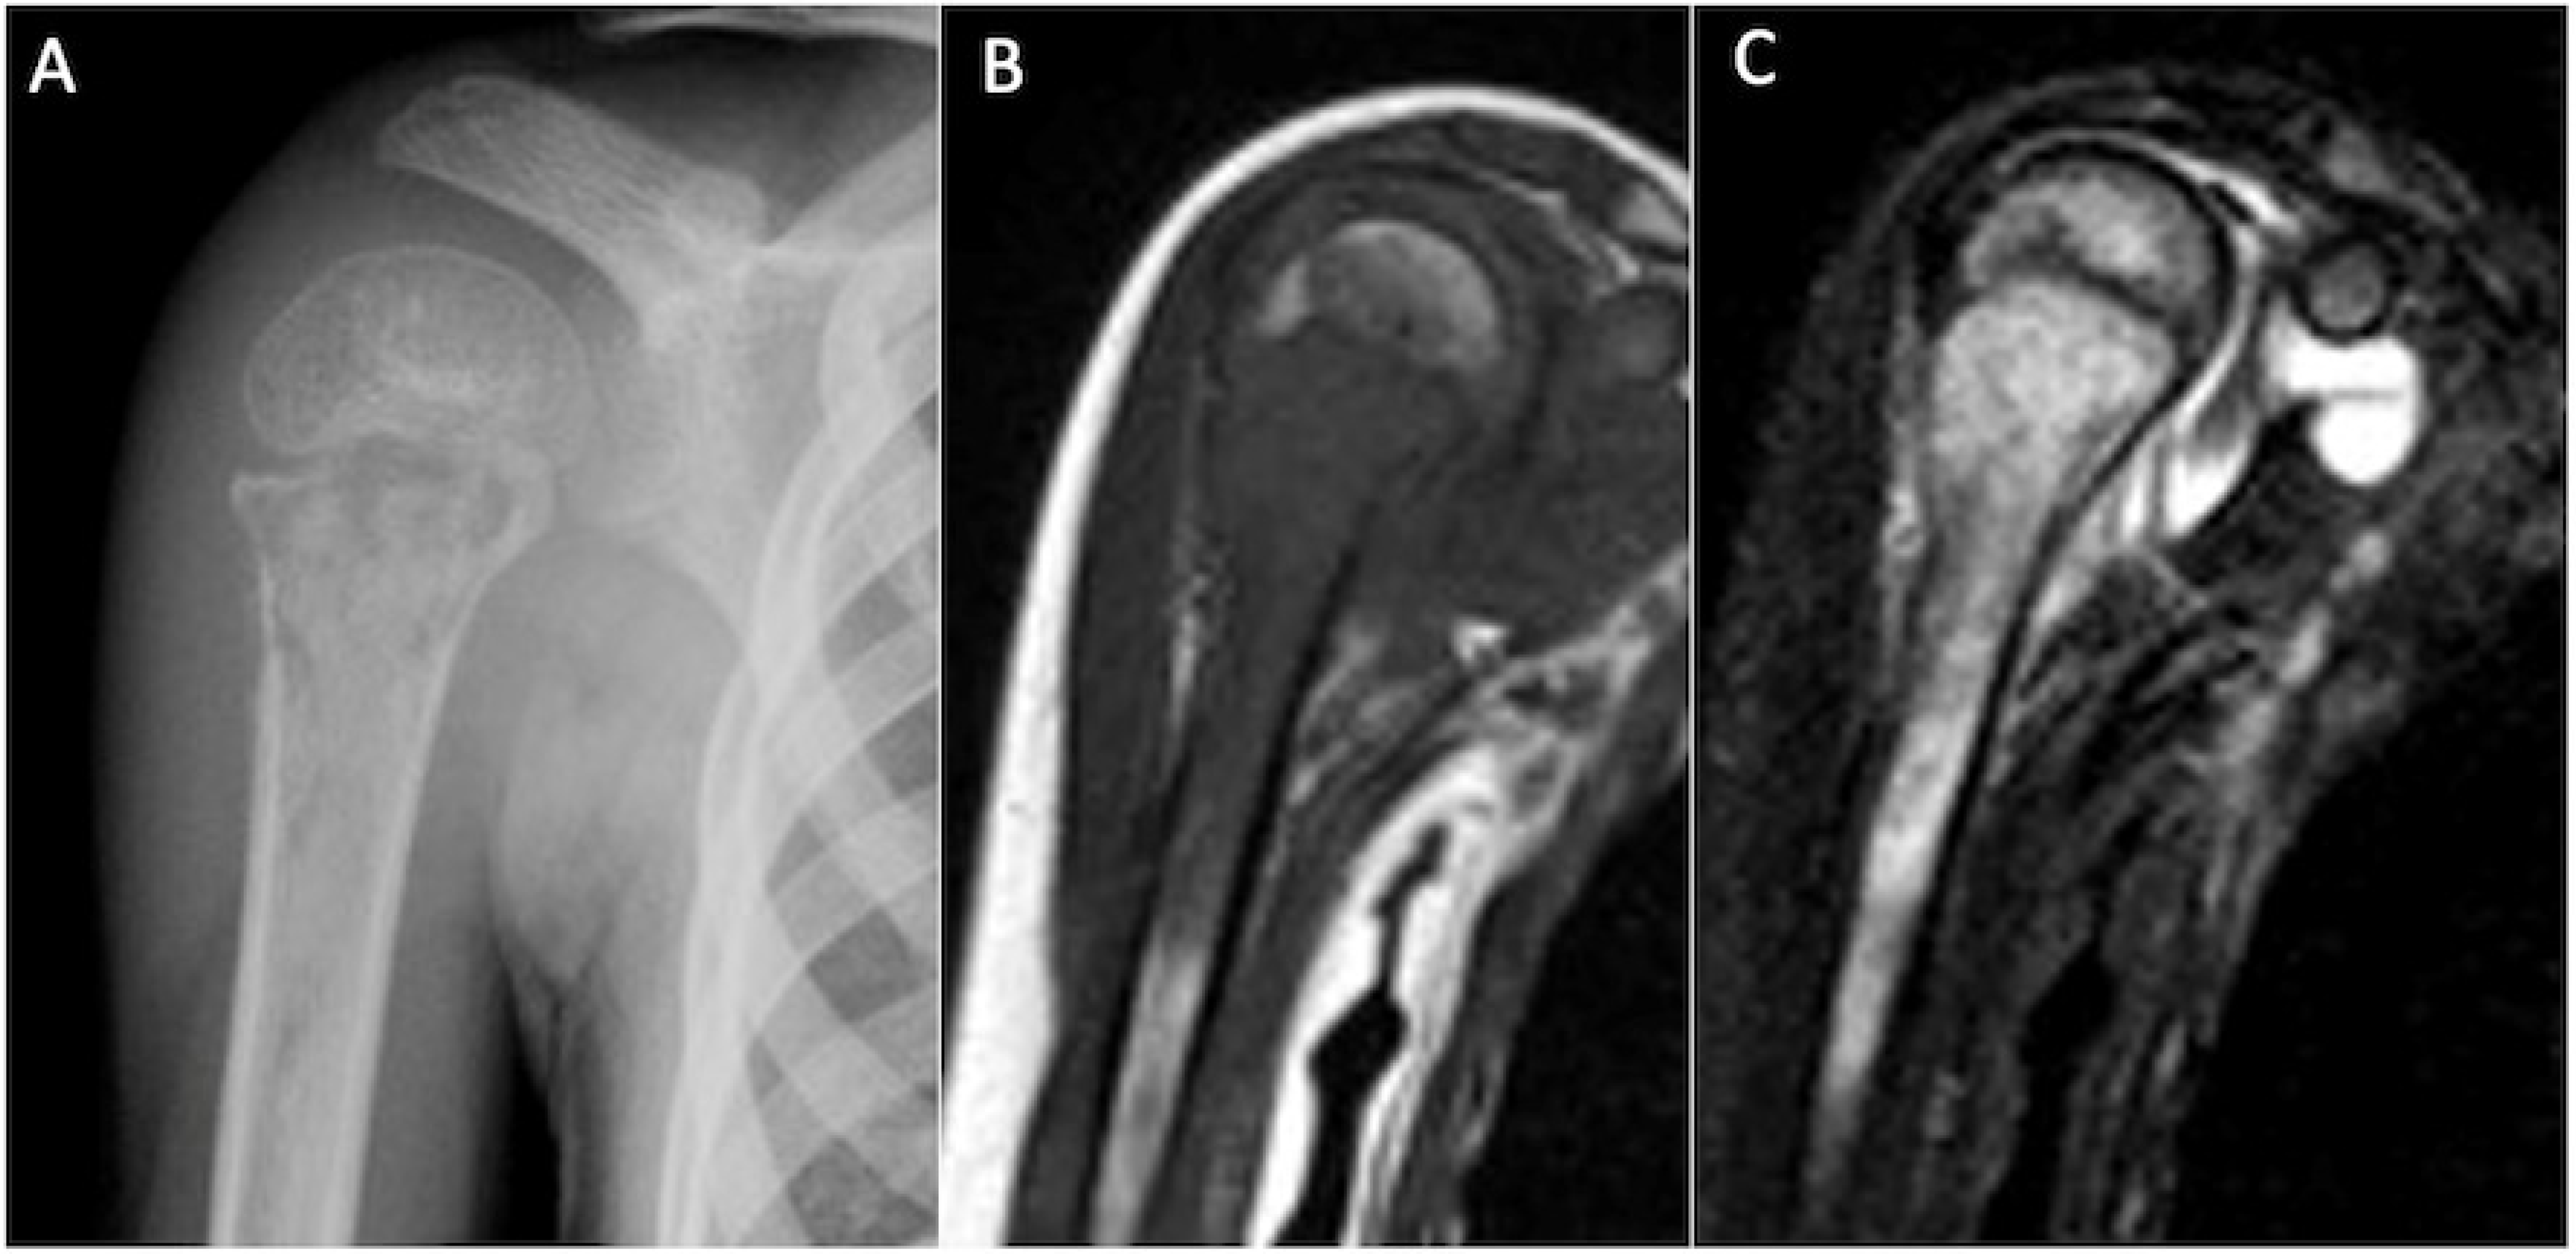

5.8. Calcific Tendinitis

- Flemming, D.J.; Murphey, M.D.; Shekitka, K.M.; Temple, H.T.; Jelinek, J.J.; Kransdorf, M.J. Osseous Involvement in Calcific Tendinitis: A Retrospective Review of 50 Cases. Am. J. Roentgenol. 2003, 181, 965–972. [Google Scholar] [CrossRef]

- Kalayci, C.B.; Kizilkaya, E. Calcific tendinitis: Intramuscular and intraosseous migration. Diagn. Interv. Radiol. 2019, 25, 480–484. [Google Scholar] [CrossRef]